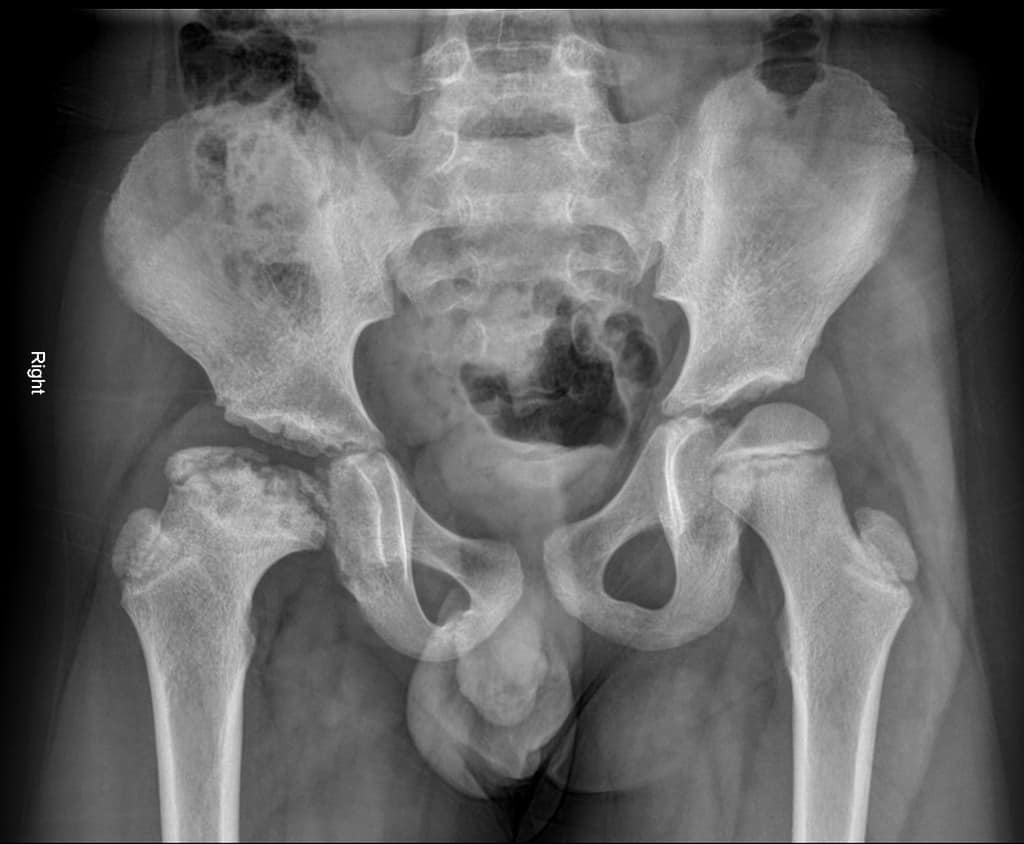

लेग काल्व पेर्थेस (Legg Calve Perthes) एक ऐसी बीमारी है, जो बचपन से ही होती है। इसमें कूल्हे के बॉल के हिस्से में खून पहुंचने में रुकावट आती है। जिससे हड्डियां काम करना बंद कर देती हैं। हड्डियों की बीमारी के कारण कई समस्याओं का सामना करना पड़ता है।

कमजोर हड्डी धीरे-धीरे टूटने लगती हैं और अपना गोल आकार खो देती हैं। शरीर धीरे—धीरे बॉल वाले हिस्से मे रक्त पहुंचाना शुरू करता है और बॉल फिर से ठीक हो जाती हैं। लेकिन अगर बॉल वाला हिस्सा ठीक होने के बाद हड्डियां अपने गोल आकार में नहीं आती हैं तो तो यह दर्द का कारण बन सकता है। हड्डी कमजोर होने के साथ उनमें फ्रैक्चर हो जाता है और नई हड्डी बनने की प्रक्रिया पूरी होने में कई साल लग सकते हैं।

इस बीमारी के कई चरण होते हैं। पहले चरण में हड्डियां काम करना बंद कर देती हैं और कूल्हों में दर्द के साथ सूजन आ जाती है। ऐसे में बच्चा दर्द की वजह से लंगड़ाकर चल सकता है। जब इस बीमारी को 1 से 2 साल की हो जाते हैं तो शरीर आर्टिक्युलर कार्टिलेज के नीचे की बेजान हड्डी को हटा देता है और उसकी जगह नई नरम हड्डी आ जाती है। इस समय हड्डियां कमजोर होती हैं।

नई, मजबूत हड्डी विकसित होने पर उसमें आकार आने लगता है। हड्डी का दोबारा बनना इस बीमारी का सबसे लंबा चरण होता है। जो कई सालों तक चल सकता है। हड्डियां धीरे-धीरे बढ़कर मजबूत होती जाती हैं और अपने पुराने आकार में आ जाती हैं। हड्डी अपने गोल आकार में आने में कितना समय लेगी, यह बच्चे की उम्र पर निर्भर करेगा।